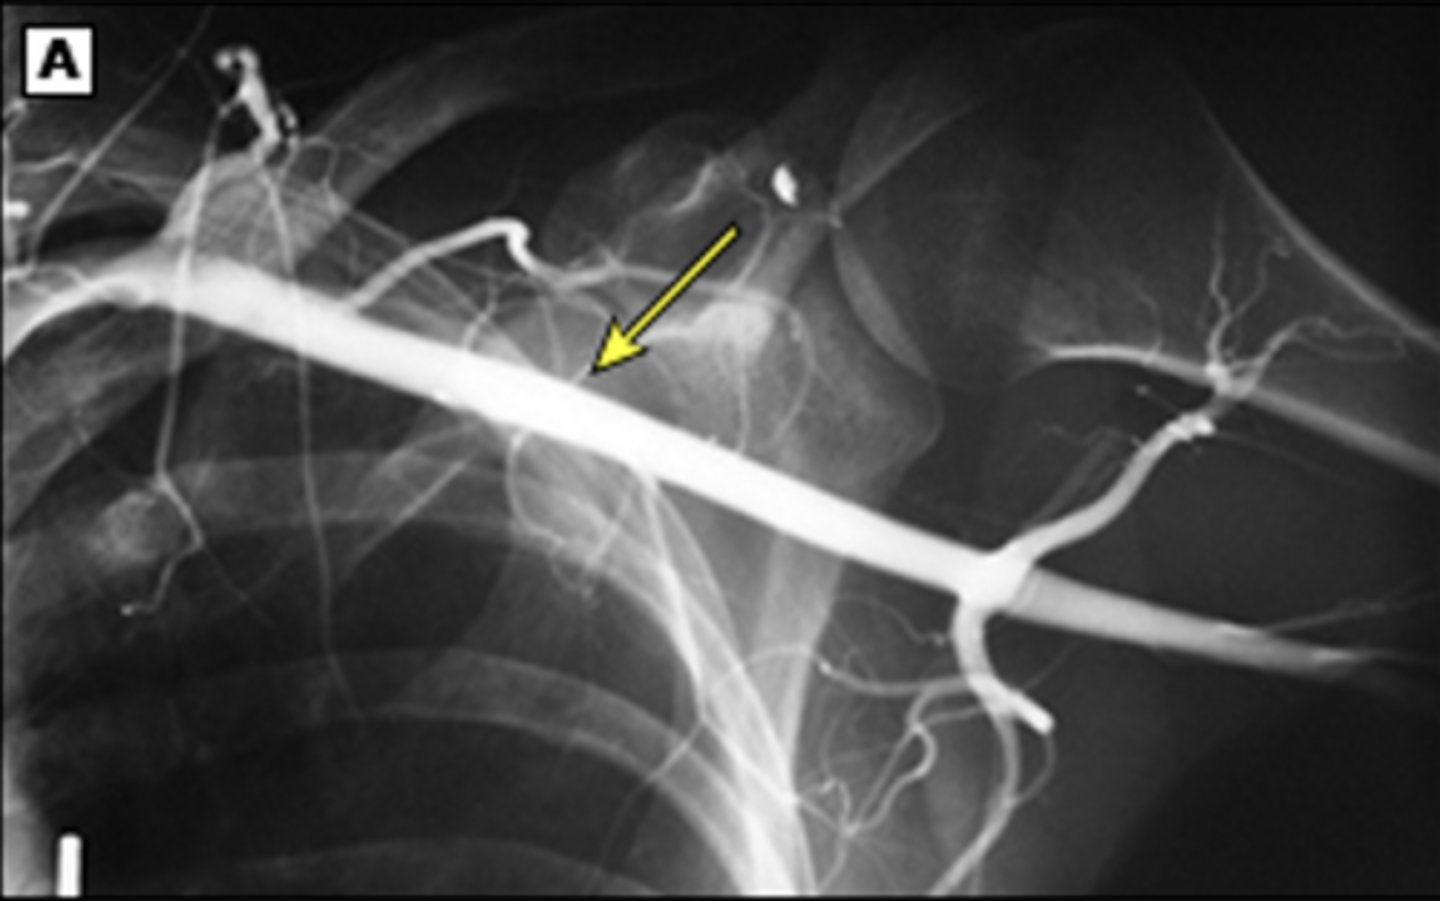

When is angiography (CT or MR) indicated in TOS?

In cases of suspected embolic disease or arterial aneurysm

embolic events, stenosis with persistent pain and vascular insufficiency, subclavian aneurysm, thrombosis with ischenia

What are the primary interventions for vascular TOS with critical ischemia?